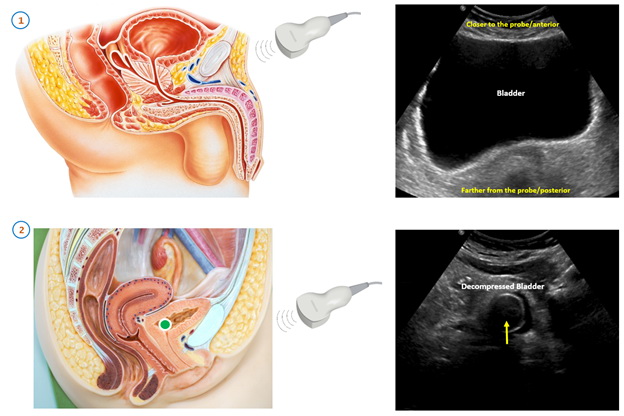

Трансабдоминальное УЗИ проводится лежа. Врач перемещает ультразвуковой датчик по нижней части живота, изменяя углы и направление, чтобы получить изображения мочевого пузыря с разных ракурсов. Во время процедуры врач может попросить пациента немного задержать дыхание или напрячь мышцы брюшного пресса, чтобы улучшить визуализацию.

Подготовка к УЗИ мочевого пузыря

Исследование проводится при наполненном мочевом пузыре. Заблаговременно до начала процедуры выпивается около 1 литра воды. Не стоит стремиться к при слишком переполненному мочевому пузырю, так как результаты могут быть менее точными.